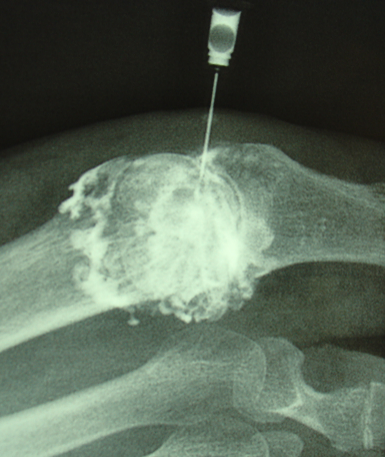

Chirurgie

Le but est de soudé l'articulationn usé (arthrodèse) à l'aide de vis ou d'une plaque